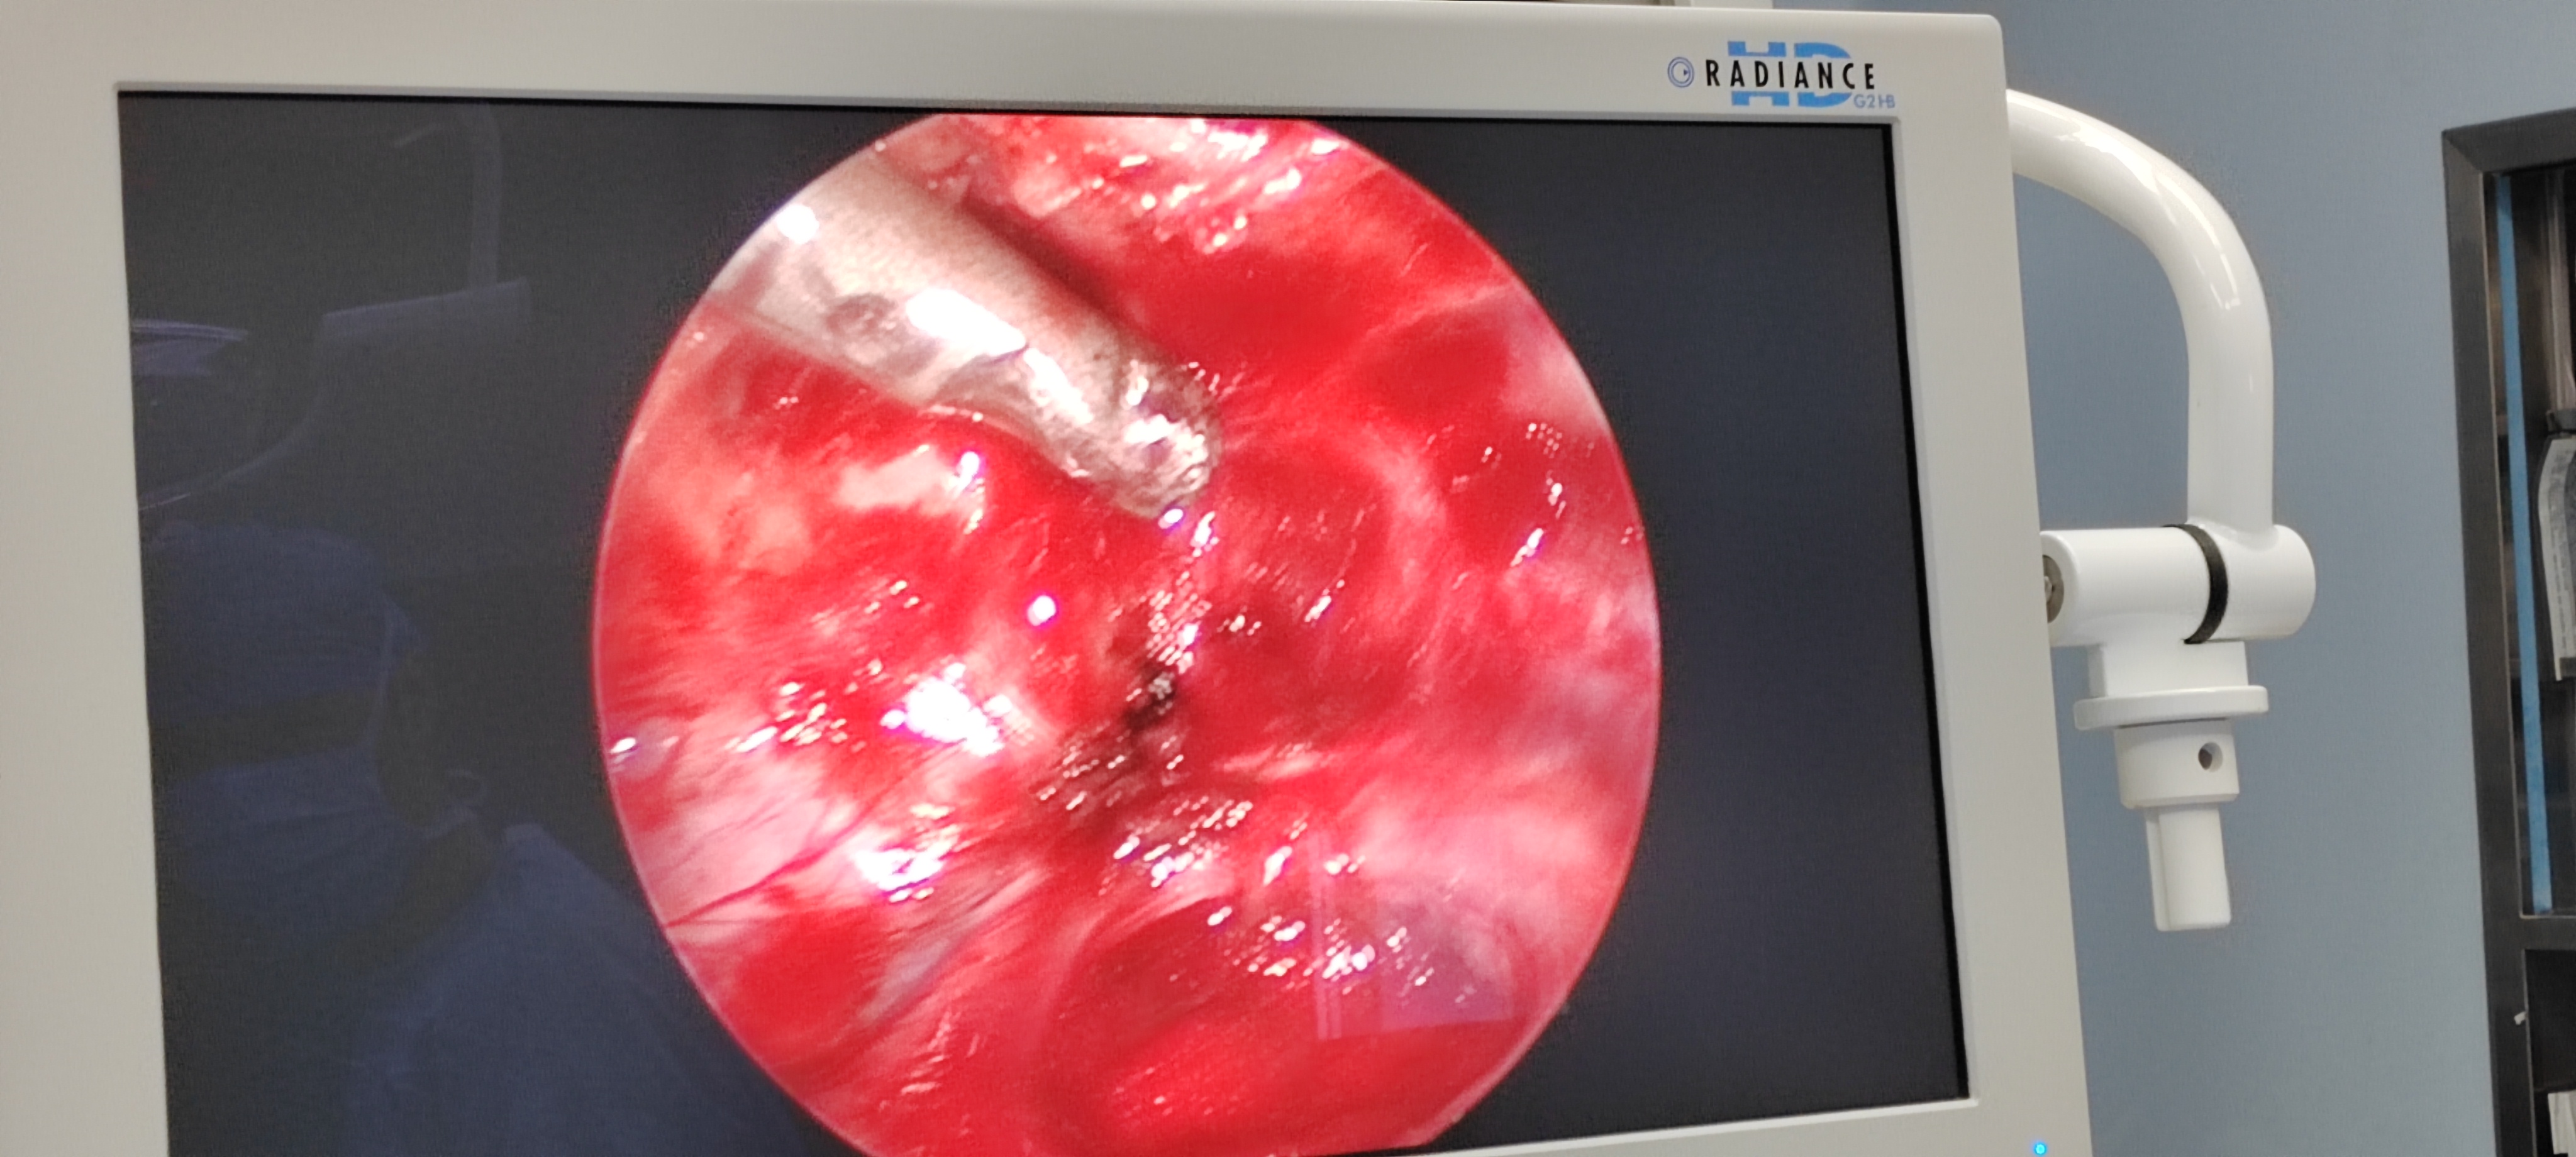

骶椎神经鞘瘤